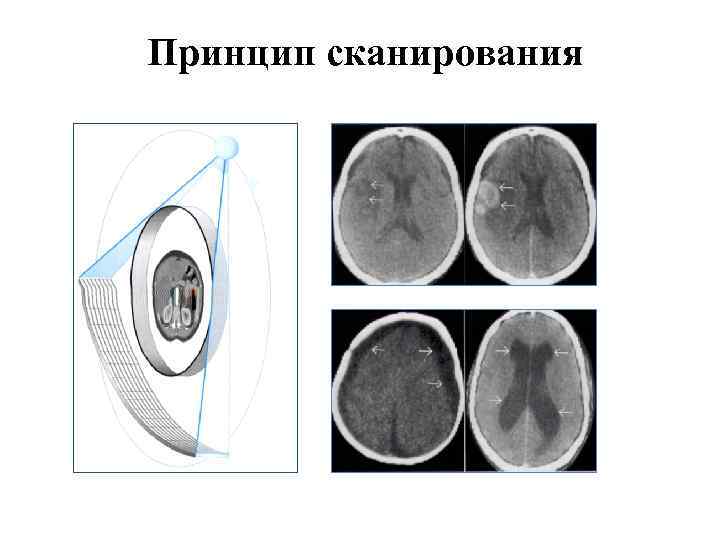

Принцип сканирования

Принцип сканирования